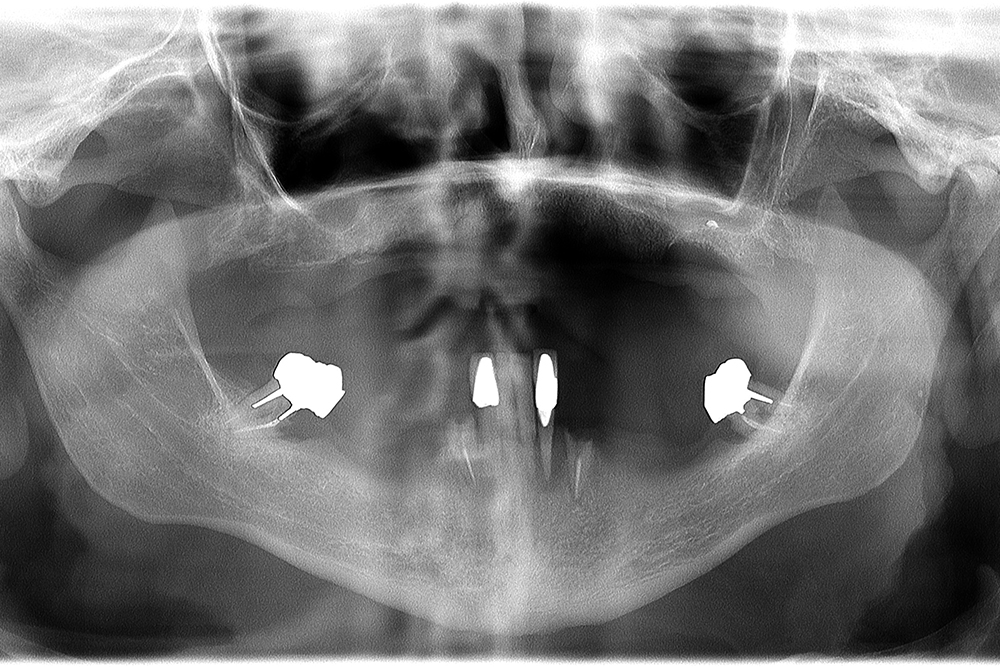

Ripristino dell'arcata superiore ed inferiore su impianti con ricostruzione estetica in zirconia e ceramica Category: Lavori ImpiantiMaggio 9, 2018Condividi questo ProgettoShare with FacebookShare with TwitterShare with Google+Share with PinterestShare with LinkedInProject navigationPreviousPrevious project:Ripristino dell’arcata superiore atroficaNextNext project:Protesi mobile superiore + Overdenture inferiore